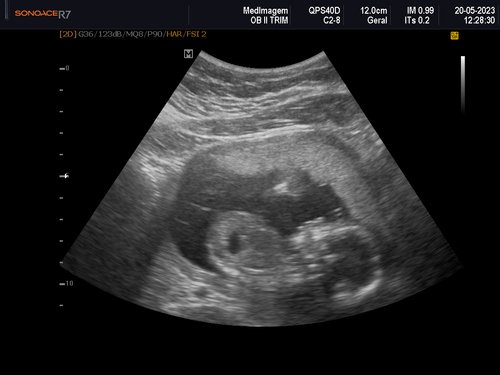

Eu tenho 27 anos estou grávida de 4 meses essa é a minha quarta gestação as minhas três últimas gestações eu perdi os bebês nunca consegui levar a gravidez adiante, eu quero muito conseguir levar essa, MINHA GRAVIDEZ É DE ALTO RISCO.

Uma amiga me deu a ideia de fazer uma vaquinha online, para conseguir fazer o tratamento no particular e o parto também, com ajuda de alguns amigos consegui arrecadar um valor e começar o tratamento no particular tive uma consulta com uma médica maravilhosa doutora Rochelle Hygino que na primeira consulta já me encaminhou para internação e para cirurgia, precisei fazer uma cerclagem no útero que é costurar o útero para segurar o bebê.